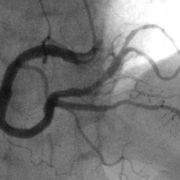

- 冠心病已经成为现代社会危及人类健康的主疾病,并且有步年化的势。在去,冠心病的断主依临床症状,心电图,B等助检查,发生的几率大。80年代以来冠影的开展使冠心病的断治疗上了